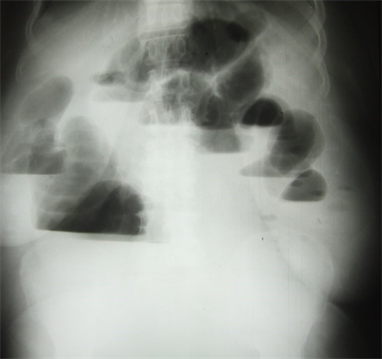

The physical examination revealed in this patient with a good general condition a diffuse, immobile and tympanic abdominal meteorism. The rectal examination did not find any tumours in the anal canal and rectal ampulla. The rectum was empty. The fingertip was not covered with blood.An oval longitudinal mass of 6 cm by 10 cm was perceived at the rigth upper lumbar part. This mass wasnot expansible to cough, not reducible, but a little sensitive. Moreover, auscultatory silence was noted at this mass (Figure 1). There was no umbilical hernia nor a white line hernia. The hernia orifices in the groin were free. An abdominal xray found multiple peripheral hydroaeric images of colonic type (Figure 2).

Figure 2. Hydroaeric levels of colonic type on abdominal x-ray.